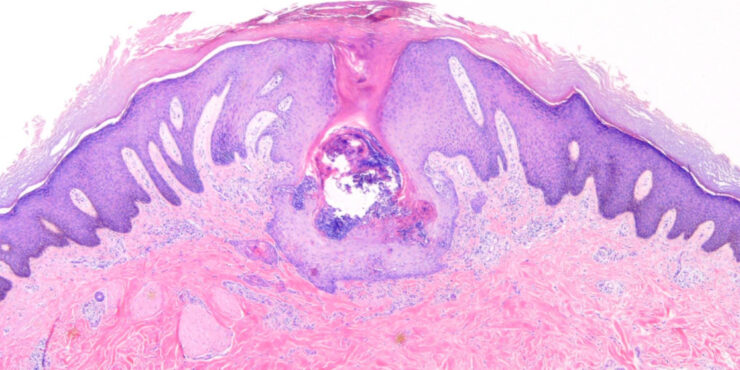

Read MoreAccessory digit =الاصبع الزائد Supernumerary Digit Polydactyly is the most common congenital digital anomaly of the hand and foot. It may appear in isolation or in association with other birth defects. Isolated polydactyly is often autosomal dominant or occasionally random, while syndromic polydactyly is commonly autosomal recessive. Polydactyly should not be considered as a single […]